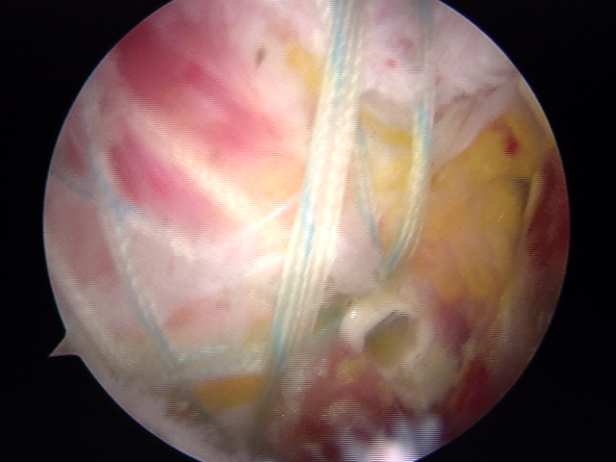

由于巨大肩袖撕裂手术难度大, 对缝合及重建的技术要求高,需要扎实的手术经验及操作技术才能完成。手术中手术团队默契配合,在关节镜下经充分松解后行肩袖修补,手术顺利完成,患者现恢复情况良好。